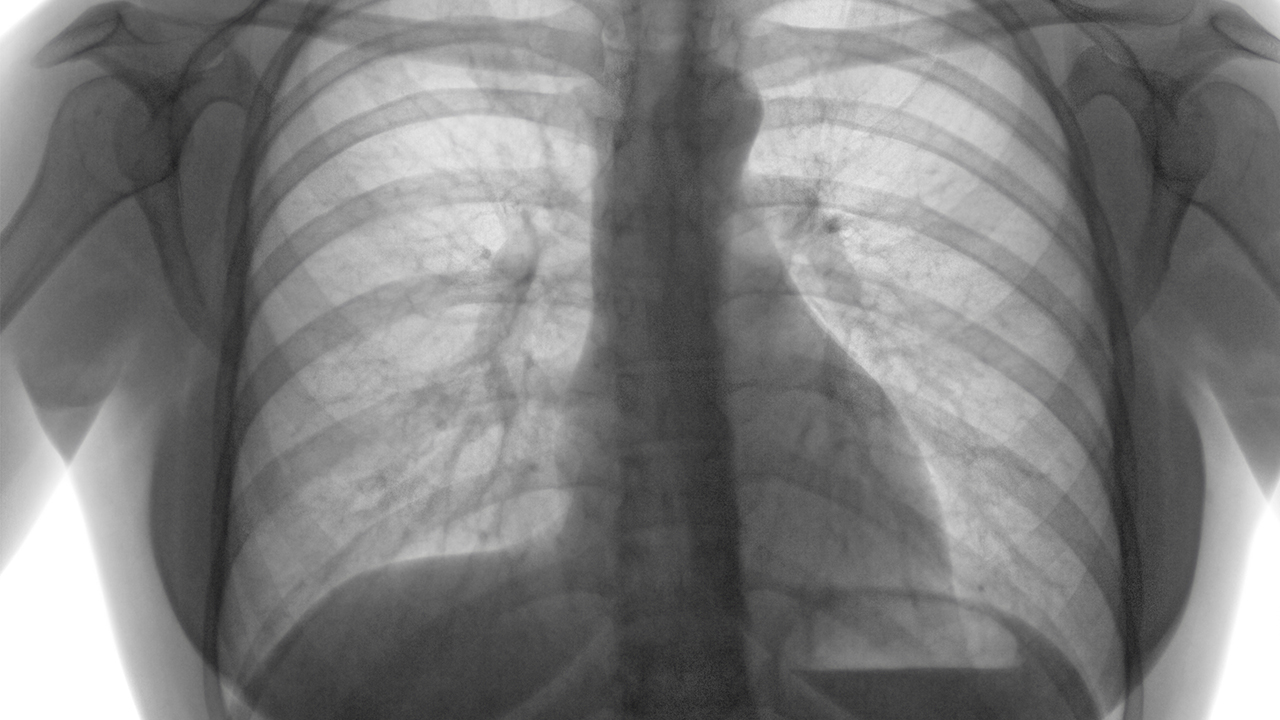

肺癌是常见的恶性肿瘤之一,其发病与吸烟、空气污染、职业暴露等因素密切相关。早期诊断和规范治疗对提高生存率至关重要,广州作为医疗资源丰富的城市,拥有多家在肺癌诊疗领域具有较高水平的医院。